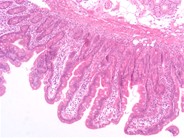

Эндоскопическое исследование является наиболее чувст-

вительным методом для подтверждения первичной лимфан-

гиэктазии. В двенадцатиперстной кишке видны белесоватые

участки – лимфангиэктазы типа «манной крупы», выступаю-

щие над слизистой оболочкой [5]. Результаты эндоскопи-

ческого исследования могут быть негативными, если пато-

логический процесс сегментарный или локализованный.

В этом случае информативна видеокапсульная эндоскопия,

которая может быть использована и у детей [2].

Двенадцатиперстная кишка, тонкая кишка: млечные капилляры слизистой диффузно расширены и окружены небольшими количествами макрофагов, нейтрофилов, лимфоцитов и плазмоцитов. Собственная пластинка диффузно инфильтрована многочисленными плазмоцитами и лимфоцитами, а также наблюдается отек слизистой. Кишечные железы расширены, заполнены базофильным пенистым материалом и иногда содержат внутриэпителиальные лимфоциты. Поверхностный эпителий во многих очагах поврежден.

Двенадцатиперстная кишка, тонкая кишка: энтерит, лимфоплазмоцитарный, диффузный, хронический, сильный, сопровождается лимфангиэктазией слизистой.